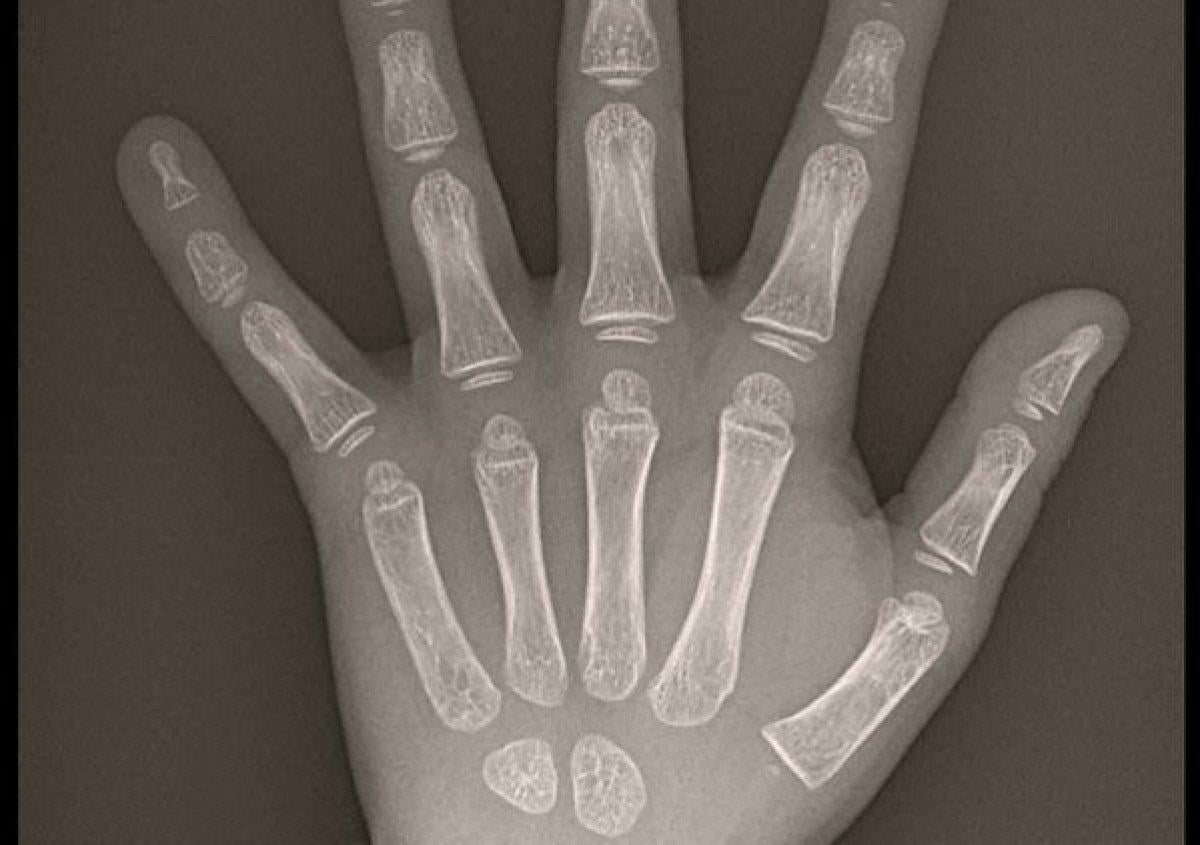

Kemik yaşı tespiti el – bilek röntgen filmlerinin radyolojik incelenmesi ile gerçekleştirilir. Bu amaçla kullanılan Greulich – Pyle Atlası kronolojik yaş gruplarına göre olması gereken standart el – bilek kemik haritalarından oluşmaktadır.

Bu yöntemde el –bilek röntgen filmi atlastaki şablonlarla karşılaştırılarak kemik yaşı tespit edilir.